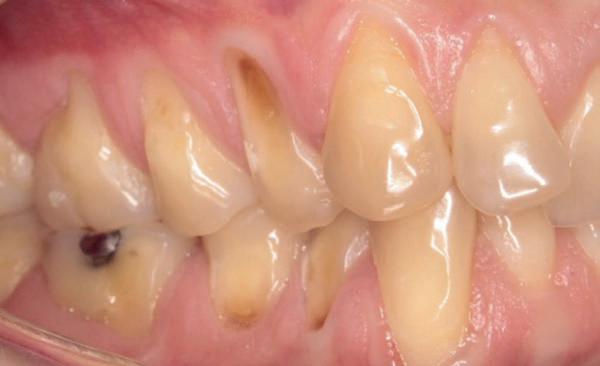

Een 48-jarige gezonde vrouw presenteerde zich in de nazorgfase 2 jaar na initiële behandeling met pockets van 6–7 mm en furcatieproblematiek bij de 47 en 46 (afbeelding 1.1 en 1.3). Bloeding bij sonderen was aanwezig, maar de patiente wilde geen chirurgische behandeling. Ze hield er een keurige mondhygiëne op na en kwam trouw iedere drie maanden voor nazorg.

De pockets werden onder lokale anaesthesie behandeld met een combinatie van ultrasoon en handinstrumentarium volgens de hierboven beschreven methode. De natriumhypochloriet/aminozuur-gel werd vijfmaal aangebracht en na iedere applicatie mechanisch verwijderd. Daarna werd de pocket gevuld met cross-linked hyaluronzuur.

Na 6 maanden was de pocketdiepte teruggebracht tot 3 mm en was er geen bloeding na sonderen waarneembaar. Een recessie van 2 mm was aanwezig. Röntgenologisch was er nieuw bot zichtbaar (afbeelding 1.2 en 1.4).

Een 62-jarige man hield in de nazorgfase een pocket van 8 mm met bloeding na sonderen mesiaal van de 36 ondanks 3-maandelijkse recall (afbeelding 2.1 en 2.3). De mondhygiëne was matig en plaque was aanwezig. Chirurgie werd geadviseerd, maar de pa-

tiënt wees dit af. Ook hier werd de pocket behandeld onder anaesthesie. De natriumhypochloriet/aminozuur-gel werd viermaal aangebracht, telkens gevolgd door ultrasone en handinstrumentatie. Tot slot werd cross-linked hyaluronzuur ingebracht. De mondhygiëne werd bijgestuurd en meneer werd gemotiveerd dagelijks interdentale ragers te gebruiken naast het poetsen.

Na zes maanden was de pocketdiepte teruggebracht tot 3 mm en was er geen bloeding na sonderen (afbeelding 2.2 en 2.4).